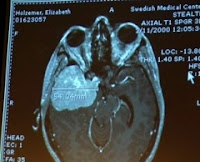

Just hours later, I sat in horror as my newly appointed neurosurgeon explained the MRI I’d had the night before. Never-before-heard terms soared over my head.

Middle third sphenoid wing meningioma.

Cavernous sinus.

Lateral ventricular compression.

You’d have to be a brain surgeon to understand any of this stuff. Thankfully, the man in the overly starched, white lab coat standing in front of me was.

I forced myself to look at the snapshots of my illuminated brain. Images of a baseball-sized mass glared back at me in defiance. My husband was a major league ballplayer at the time, but I never imagined I’d be looking at the equivalent size of one in my head. Surely there had been a mix up. I was healthy, only 32 and trying to start a family. Maybe this explained my struggles to become pregnant the past year.

“You’ve probably had this tumor for over a decade,” my neurosurgeon solemnly announced.